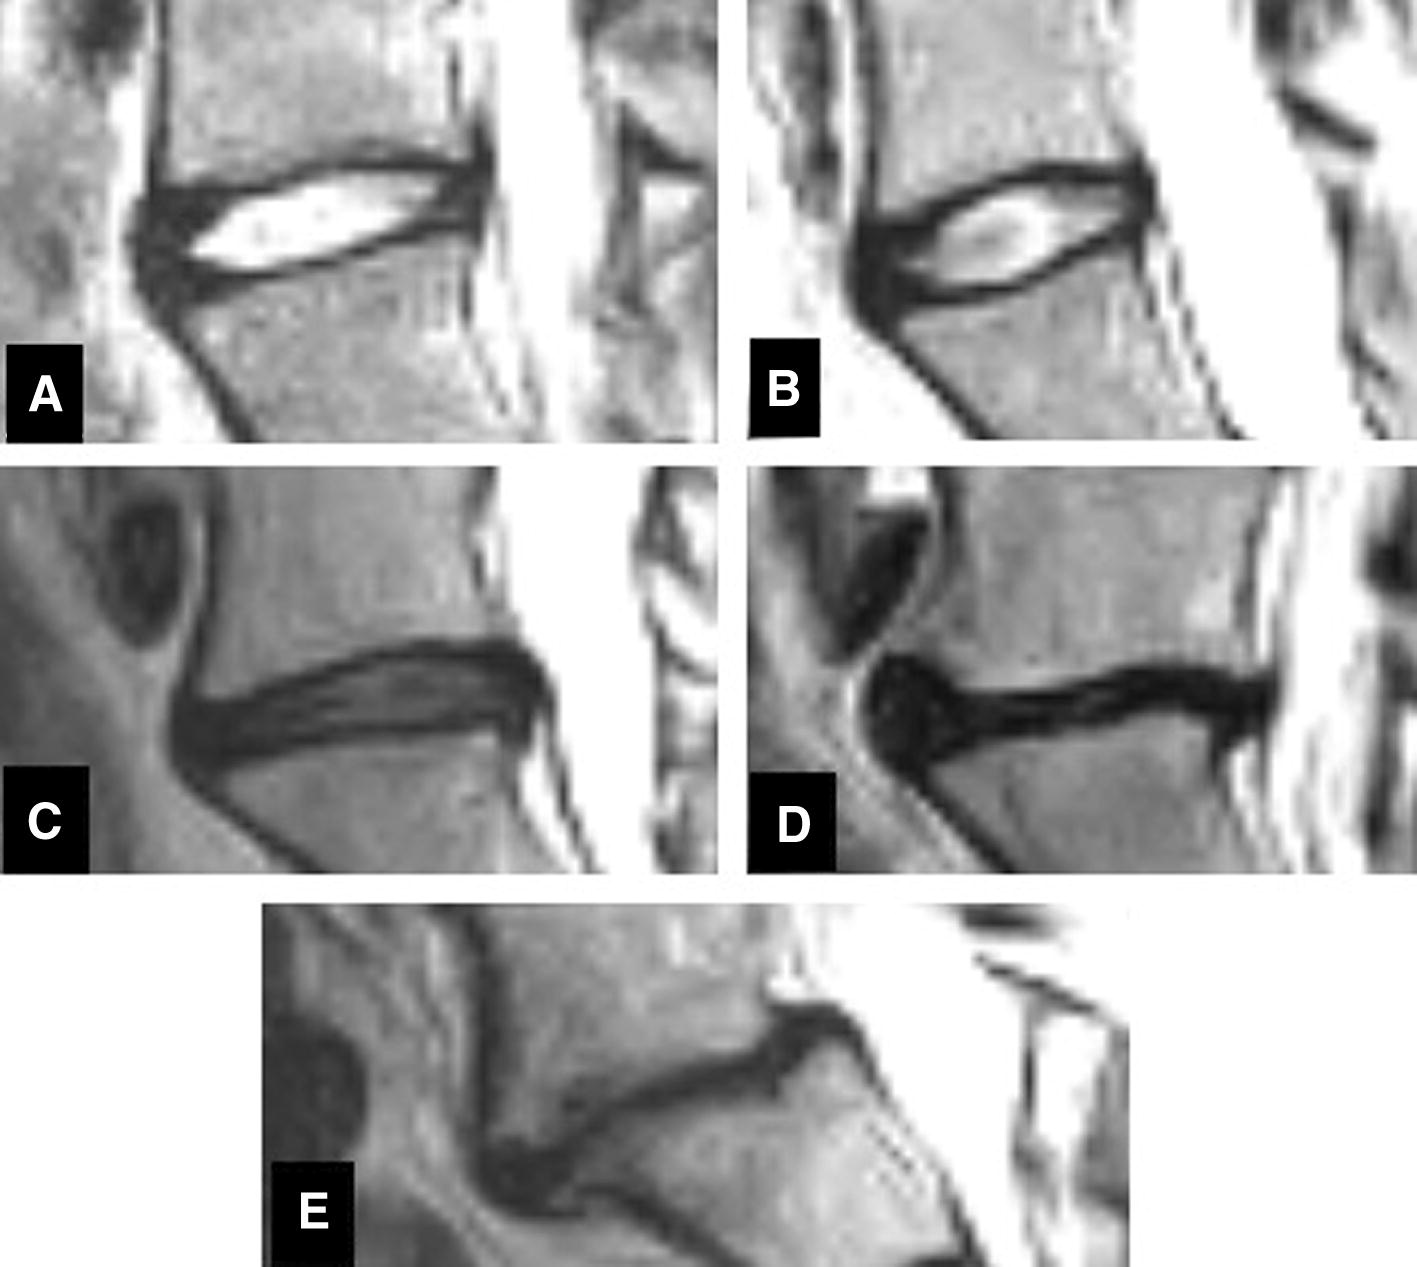

Purpose This study aimed to evaluate facet joint parameters and osteoarthritis grades, and segmental angular and translational motions among different grades of L5/S1 intervertebral disc (IVD) degeneration. Methods This retrospective study analysed kinematic magnetic resonance imaging (kMRI) images of the lumbar spine of 214 patients with low back pain. Degenerations of the L5/S1 IVDs and facet joints osteoarthritis were assessed using the Pfirrmann and Pathria grading scales, respectively. Facet joint parameters included facet joint angle and facet joint space width. Angular and translation segmental motions were measured using MRI Analyzer software. Results The mean age of the studied patients was 44.1 ± 13.9 years. Patients with L5/S1 disc degeneration were associated with higher odds of facet joint osteoarthritis (odds ratio = 2.28, 95% confidence interval = 1.23–4.23, P = 0.008). There was a positive correlation between L5/S1 disc degeneration grade and the facet joint grade (r = 0.365, P > 0.001). Grade IV facet joint osteoarthritis did not appear in grades I or II disc degeneration (P > 0.001). The average facet joint width decreased significantly with increasing Pfirrmann grading (P = 0.017). The difference in facet joint angle between groups was not statistically significant (P = 0.532). The differences in the angular and translational motions were not statistically significant (P = 0.530, and 0.510, respectively). Conclusion A positive correlation exists between L5/S1 disc degeneration and facet joint osteoarthritis grades. The facet joint space width decreases significantly with increasing grade of disc degeneration.

• Disc degeneration: Pfirrmann classification

• Facet joint osteoarthritis: Pathria classification